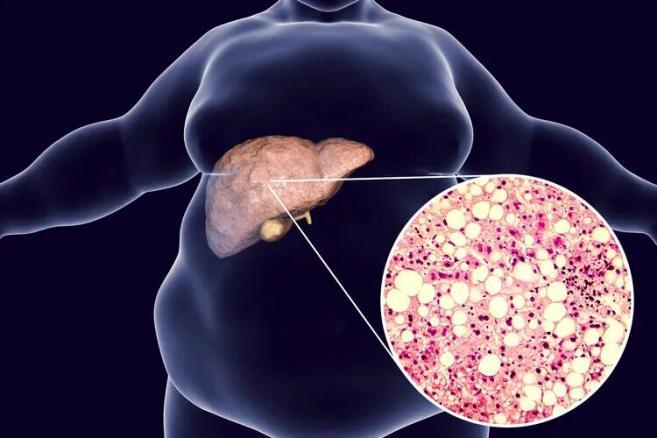

脂肪肝是指各种因素所致的肝细胞内脂肪堆积过多,正常情况下肝内脂肪占肝湿重的3~4%。当这个比例>5%时,即为脂肪肝。

2023年发布的一项针对中国575万余份体检的分析研究发现,脂肪肝、重度脂肪肝的患病率分别为44.39%、10.57%。不加以控制的话,脂肪肝会逐渐演变成脂肪性肝炎、肝纤维化、肝硬化,乃至肝癌。

美国肝病研究学会在《肝病学》上发表的一项研究也指出,脂肪肝会让肝脏长期处于炎症状态下,容易引起肝细胞癌变。且这些患者身上多伴有代谢综合征,会促进其他部位发生癌症,会给身体带来全方位的伤害,给癌症的发生提供“温床”。